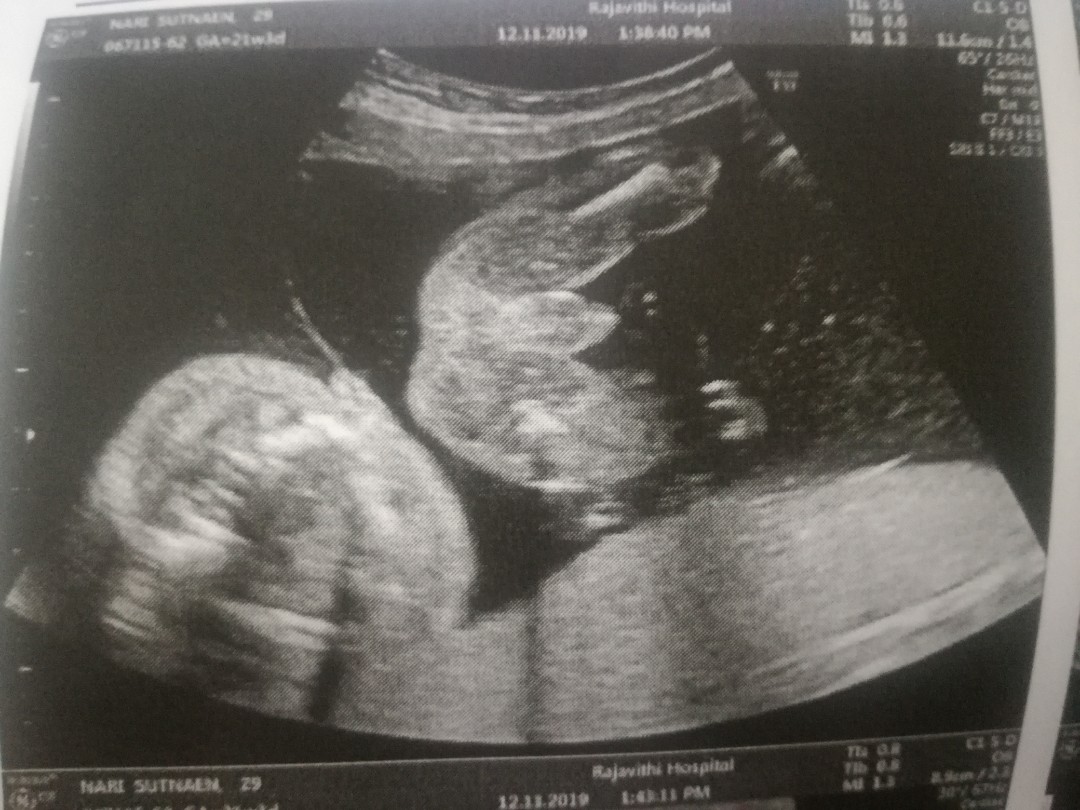

ใบซาวด์

ขอดูใบซาวด์แม่เพศ ชาย หญิง หน่อยค่ะ

ผ.ชค่ะภาพสุดท้าย

หมอบอกผู้ชายค่ะ

ผู้ชายคะ